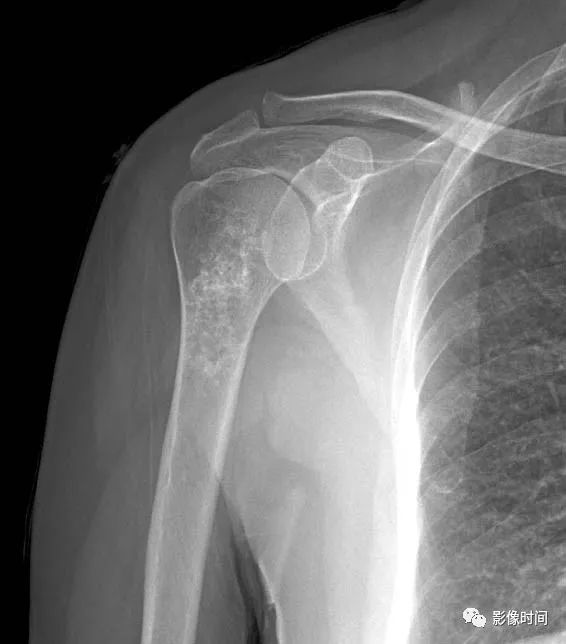

(一)瘤软骨钙化:瘤软骨常表现为环状钙化, 是诊断软骨类肿瘤较为可靠的影像学征象。环状钙化形成于环状软骨、以及软骨小叶边缘的软骨基质。钙质沉着可呈小点状、小条状、半环状或弧形;亦可浓密相连、重叠呈菜花状。钙化环的形态和密度可反映瘤组织分化程度, 通过观察钙化环的形态和密度,有助于良恶肿瘤的鉴别。

良性瘤软骨之瘤细胞分化好、生长缓慢、血供充分, 钙化环完整,密度高, 边缘清楚。良性软骨类肿瘤如骨软骨瘤(图 35)、软骨母细胞瘤(图 36)、内生软骨瘤(图 37)等均可于瘤组织内发生环形钙化。

恶性瘤软骨则呈密度淡薄, 边缘模糊的不规则钙化,恶性骨肿瘤的环形钙化,最多见于软骨肉瘤(图 38),其次是骨肉瘤。CT 是发现肿瘤内软骨钙化最为敏感的检查方法。

图 35  瘤软骨钙化:骨软骨瘤

图 36  瘤软骨钙化:软骨母细胞瘤

图 37  瘤软骨钙化:内生软骨瘤

图 38  瘤软骨钙化:软骨肉瘤